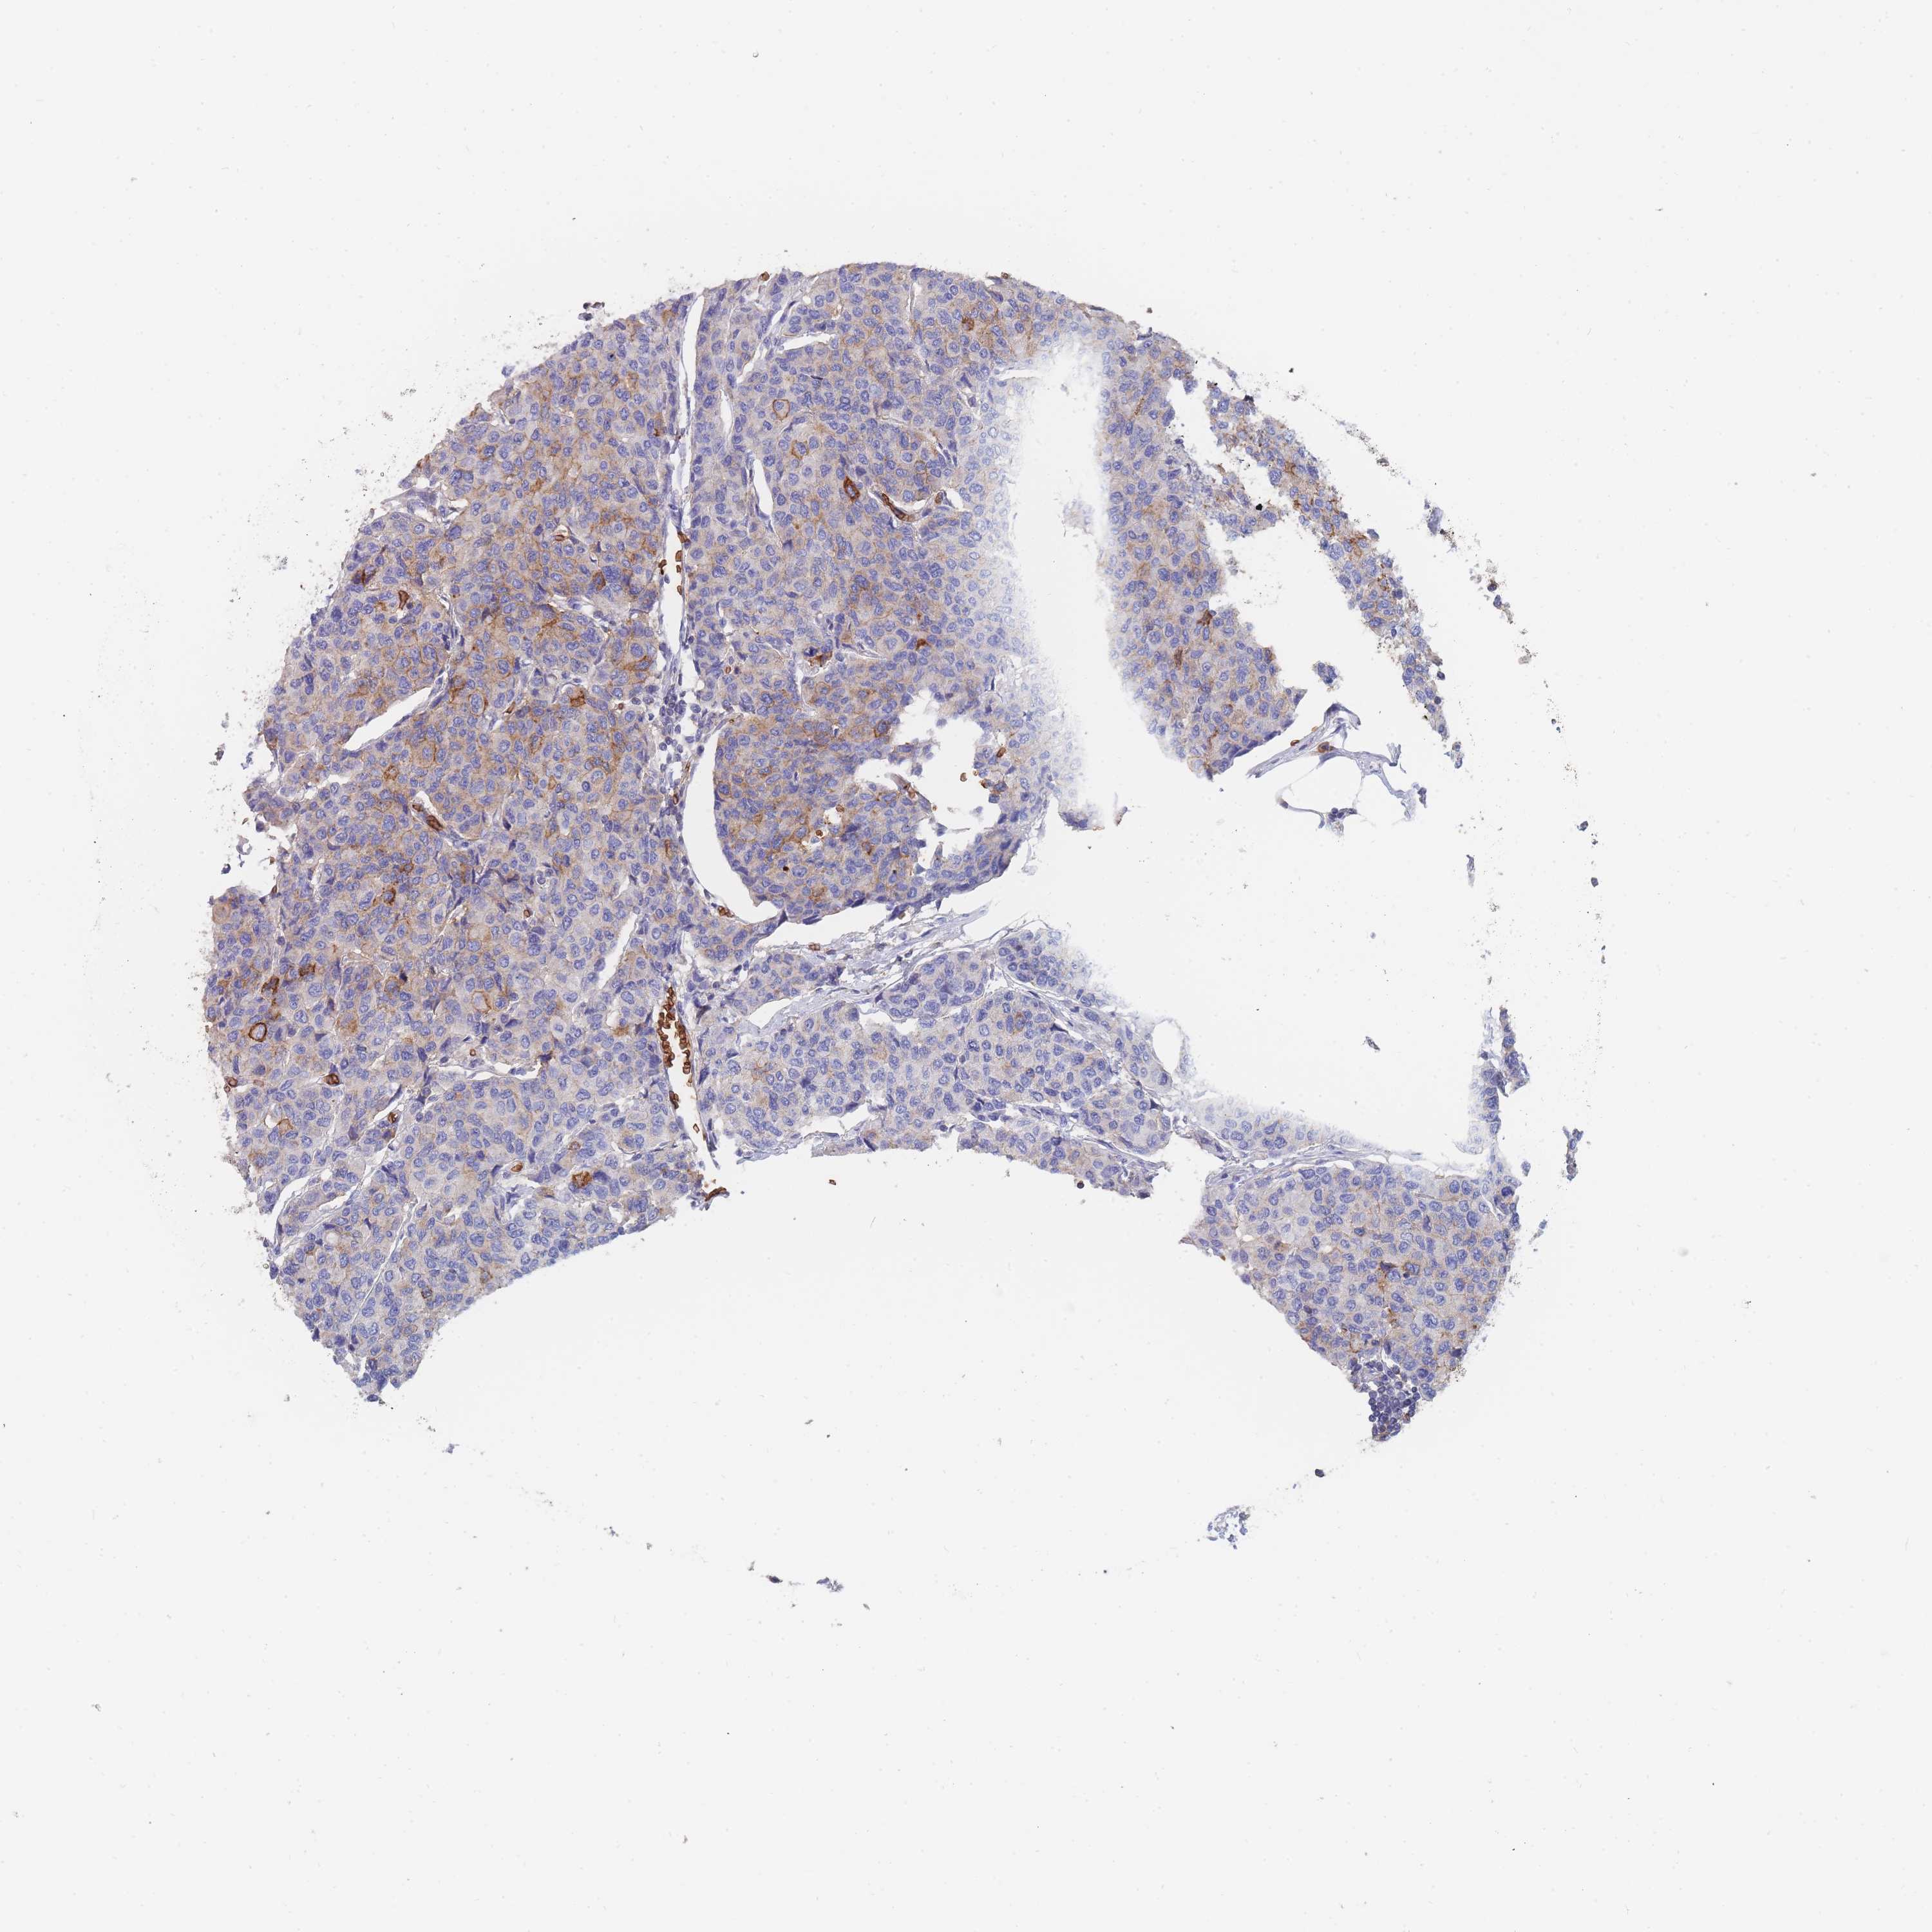

BRCA TCGA BRCA VALIDATION PROTEIN EXPRESSION

ANTIBODIES

AND

VALIDATION